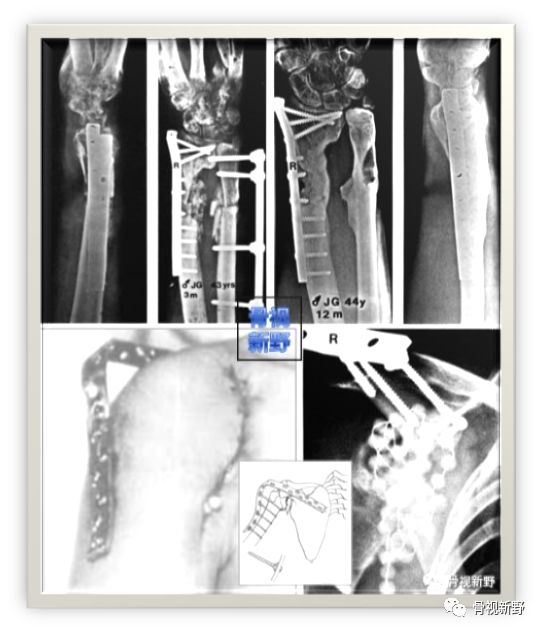

锁骨感染性骨不连的LCP外固定

case